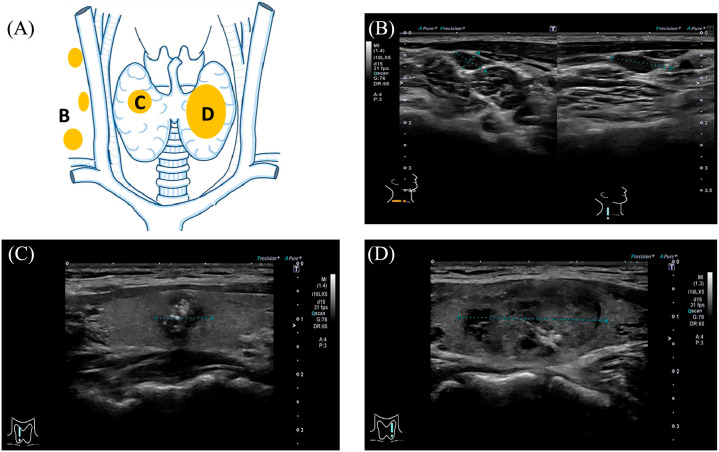

Multiple endocrine neoplasia type 2B (MEN2B) is a rare autosomal dominant disorder caused by germline pathogenic RET variants. On the other hand, Charcot-Marie-Tooth disease (CMT) is a hereditary neurological disorder, characterized by distal muscle weakness and sensory loss, with approximately 100 identified causative genes. Herein, we report a de novo RET mutation in a patient presenting with clinical features of both MEN2B and CMT. The patient, a 22-year-old woman, had a history of lower limb muscle weakness, with no family history of MEN2B or CMT. The patient was being treated for a thyroid gland neoplasm. Genetic testing of the medullary thyroid carcinoma revealed a previously unreported RET germline variant, p.M918W (RET: c.2752_2753delinsTG, p.Met918Trp). The novel p.M918W RET variant was associated with concurrent MEN2B and CMT. This finding was unexpected as MEN2B typically manifests with distinct features, such as marfanoid habitus and mucosal neuromas, but not with muscle weakness, as seen in CMT. Based on this finding, the plausible role of the p.M918W mutation as a shared pathway for both MEN2B and CMT warrants further investigation.